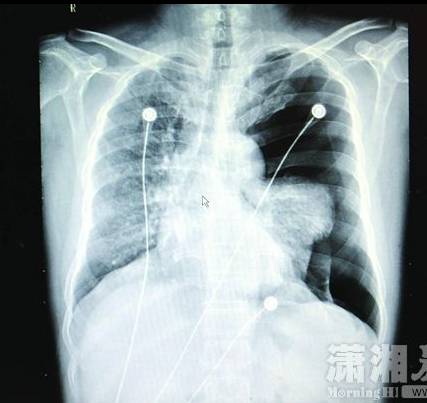

【byb.cn 】(來(lái)源:瀟湘晨報(bào))1月14日,長(zhǎng)沙市中心醫(yī)院。近日,45歲男子李某K歌太猛,導(dǎo)致左側(cè)肺大皰破裂引發(fā)了氣胸。

長(zhǎng)沙汽車南站45歲男子李某K歌太猛,導(dǎo)致肺大皰破裂引發(fā)了氣胸,被家人緊急送到醫(yī)院搶救。1月14日,瀟湘晨報(bào)記者從長(zhǎng)沙市中心醫(yī)院獲悉,經(jīng)開胸手術(shù)后李某才保住性命。

"患者入院時(shí)呼吸、講話很困難,不能平臥,左手緊緊捂著胸口,有明顯的呼吸困難、胸痛等癥狀。緊急檢查發(fā)現(xiàn),其左側(cè)重度氣胸,左肺已壓縮60%以上,心臟受壓移位;若不及時(shí)處理,很可能危及生命。"長(zhǎng)沙市中心醫(yī)院胸心外科副主任醫(yī)師彭建明介紹,人的胸膜腔是密閉的、不含空氣的潛在性腔隙,在一些先天因素的影響下,有部分小肺泡會(huì)逐漸融合成一個(gè)巨大的、沒(méi)有氣體交換功能的肺大皰,導(dǎo)致肺組織彈性下降;當(dāng)劇烈咳嗽、踢足球、提重物、大笑、K歌等用力過(guò)猛活動(dòng)時(shí),肺內(nèi)壓力突然增加,很可能導(dǎo)致肺大皰破裂發(fā)生氣胸,氣體進(jìn)入胸膜腔導(dǎo)致肺葉被壓縮,從而引起呼吸困難,嚴(yán)重時(shí)可危及生命。彭建明說(shuō):"醫(yī)生在全麻胸腔鏡下為李先生行微創(chuàng)手術(shù),術(shù)后恢復(fù)情況良好,順利出院。"